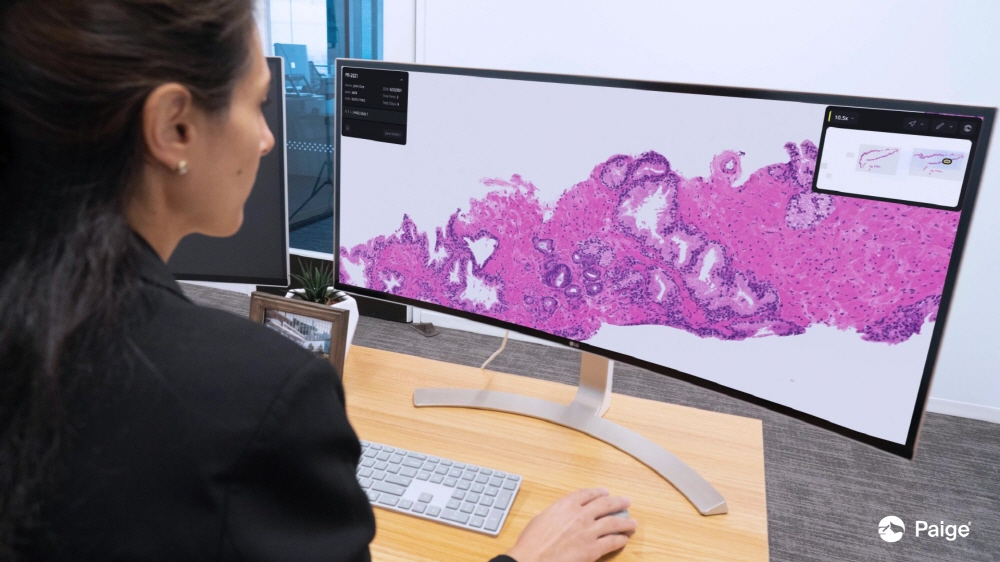

남성 생식기인 전립선에 발생하는 전립선암은 비흑색종 피부암을 빼고 미국 남성에게 가장 많은 암으로 암으로 인해 사망하는 남성 사망 원인도 상위권에 위치하고 있다. 2017년 설립된 AI 기업인 페이지(Paige)는 9월 21일 회사 전립선암 검출용 AI인 페이지 프로스테이트가 혁신적인 의료 기술에 대한 신청(De Novo)에 따르면 FDA는 승인을 얻었다고 보고했다. 발표에 따르면 생검된 전립선 조직 슬라이드 이미지를 분석해 암을 특정하는 AI로 FDA 승인을 받은 건 페이지 프로스테이트가 처음이다.

승인에는 FDA가 전문의 16명이 참가한 임상시험 결과를 평가했다. 이 시험은 악성종양이 있는 전립선 생검 슬라이드 사진 171장과 양성 슬라이드 사진 365장을 포함한 슬라이드 527개가 사용되어 각 전문의는 각각 슬라이드를 페이지 프로스테이트 어시스트 있음과 없음으로 분석했다.

테스트 결과 페이지 프로스테이트는 암 검출율을 89.5%에서 96.8%로 7% 포인트 향상시킨 한편 양성 종양 검출율에 영향을 주지 않았다는 걸 확인했다. 또 페이지 프로테스테이트 지원을 받은 의사는 위음성 진단이 70% 거짓, 긍정적인 진단이 24% 감소했다며 이런 효과는 전문의 경험과 검사는 원격 여부 등에 좌우되지 않았다고 한다.

FDA 의료기기 방사선 보건센터에서 체외 진단과 방사선 보건 부문 디렉터인 팀 스텐젤(Tim Stenzel) 박사는 페이지 프로스테이트에 대해 병리학과 전립선암 등 질벼잉 의심되는 조직 생검을 매일처럼 진단하고 있다며 AI가 생검 스캔 이미지에서 암이 의심스러운 영역을 특정하는 건 적절한 병리학 치료로 이어질 진단에 도움이 될 것이라고 설명했다.

페이지 측은 이번 FDA 승인은 병리 컴퓨터 지원 진단에 새로운 시대가 시작됐다는 걸 의미한다고 강조했다. 관련 내용은 이곳에서 확인할 수 있다.